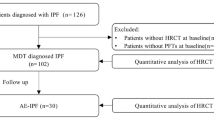

The electronic literature search yielded 244 potential studies. After duplicates were removed by Endnote 20, 178 studies remained. Eight studies were excluded because the full text could not be obtained. After reviewing 170 full tests, 111 studies were excluded because the target disease was not IPF, 10 studies were excluded because the detection method was not computed tomography (CT), 25 studies were excluded because CT patterns were not evaluated by CALIPER, 5 studies were excluded because they did not detect the relationship with PFT, mortality, or outcome in clinical trials, and 8 studies were excluded because they were reviews or conference abstracts. One Chinese study was not included because there was inadequate interpretation of the data. Ultimately, 10 studies met the inclusion criteria. Figure 1 presents a flow diagram of the search.